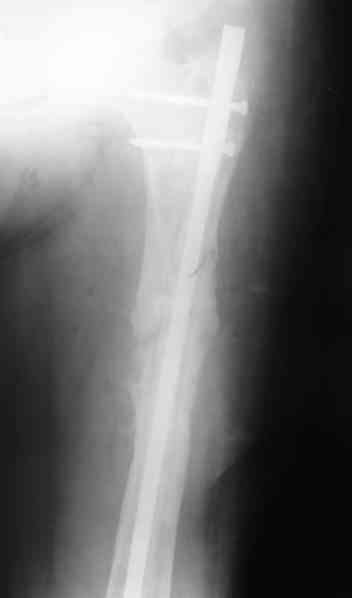

1, 2, 3, 4 - рентгенограммы бедра от 8 августа этого года (через четыре месяца после операции);

В качестве демонстрации лечения канального остеомиелита бедренной кости представляем пациентку (см. parts 2 и 3), которая как раз сегодня была у нас на контрольном осмотре. В мае этого года мы произвели ей фиксацию бедренной кости штифтом-спейсером по поводу ложного сустава и канального остеомиелита бедренной кости. Через 4 недели после операции свищи закрылись. Сейчас она ходит с полной нагрузкой на конечность.

4, 5, 6 - рентгенограммы бедра и фотографии пациентки (прошу прощения за низкое качество рентгеновских снимков) от 7 сентября 2007 г.

Мы уже накопили скромный опыт использования данного способа лечения. С апреля этого года мы выполнили 21 подобную операцию. Мы попробовали применять этот способ при фиксации переломов на фоне различных различных форм остеомиелита, при нагноении мягких тканей и в качестве первичной фиксации при тяжелых открытых переломах при переломах голени, бедра и плеча. В подавляющем большинстве случаев получены хорошие результаты.